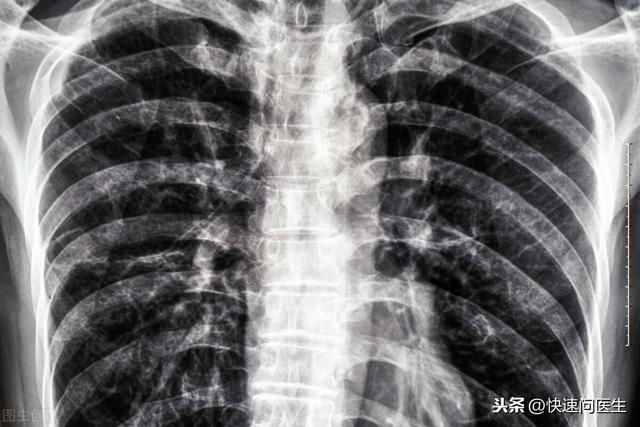

2、胸透

对于备孕期的女性而言 , 胸透也要尽量少做 。 有相关实验研究表明 , 人类受精卵在子宫内膜植入后形成胚胎的前期阶段 , 如果经常受到X射线刺激且刺激的量较大 , 可加大胚胎发生畸形的风险 。

再者 , 对胚胎较大的一个影响是可影响到其正常发育 。 也就是说发生体重过轻 , 或造成智力或生殖功能障碍等 。 比较严重的后果就是可造成先兆流产 。